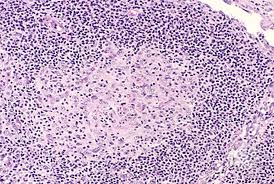

2015 july 3, luis f. J cancer res immunooncol 5: Angioimmunoblastic t cell lymphoma (aitl) presents in older patients and the median age at diagnosis is approximately 60. In aitl, the tumor cells are often accompanied by a mixed inflammatory infiltrate. Angioimmunoblastic lymphadenopathy (aild) with dysproteinemia;

Angioimmunoblastic t cell lymphoma (aitl) is a peripheral t cell lymphoma characterized by systemic disease, a polymorphous infiltrate involving lymph nodes, and a prominent proliferation of.

In aitl, the tumor cells are often accompanied by a mixed inflammatory infiltrate. Blood diseases, cancer diseases, immune diseases, rare diseases. Angioimmunoblastic t cell lymphoma microenvironment. 2015 july 3, luis f. Angioimmunoblastic lymphadenopathy (aild) with dysproteinemia;